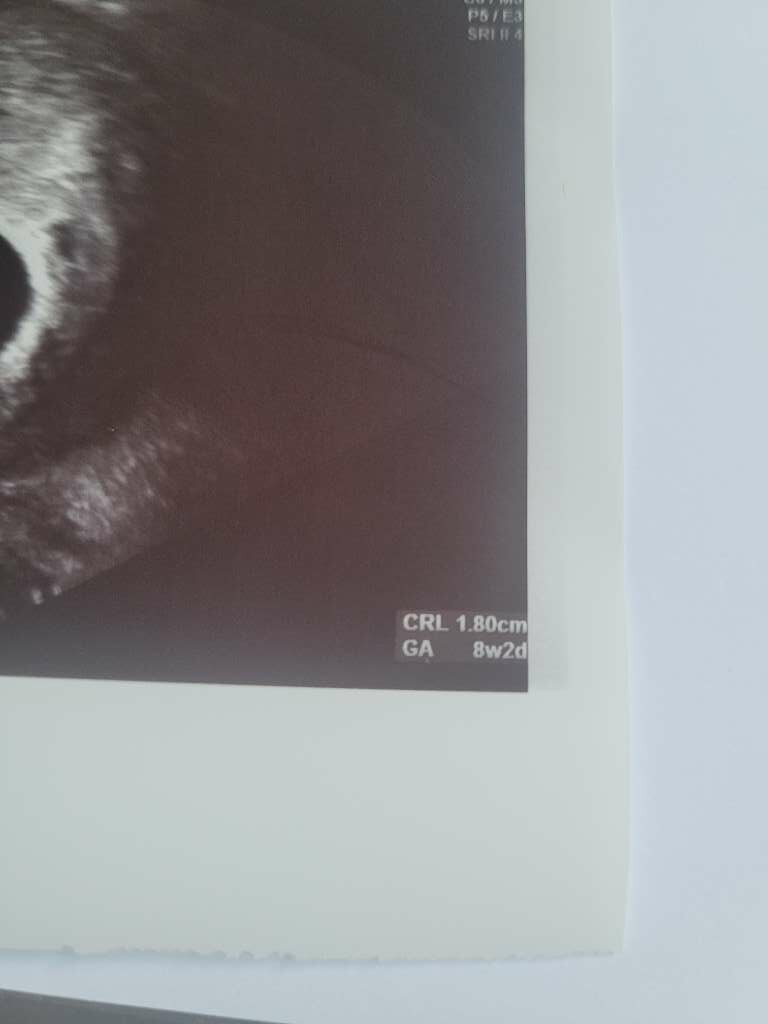

Jakie cudeńko piękne!My już po wizycie. Dzidziol rośnie, ma już ok 2,5cm![]()

Masz zwykle podsumowanie najpierw i dwie daty (wiek ciąży). Jedna z om a druga z pomiarów z usg.Słuchajcie to co jest wpisane na zdjęciu z usg - który tydzień - to jest to co określa lekarz i sobie wpisuje, czy wg tego jak mierzony jest zarodek/płód i jak wypada wg norm? i aparatura określa ten wiek?

nie mam tego... mam.na każdym zdjęciu tylko w prawym dolnym rogu wiek ciążyMasz zwykle podsumowanie najpierw i dwie daty (wiek ciąży). Jedna z om a druga z pomiarów z usg.

To mi na zdjęciu wiek zgadza się z pomiarami usg, nie z om.nie mam tego... mam.na każdym zdjęciu tylko w prawym dolnym rogu wiek ciąży